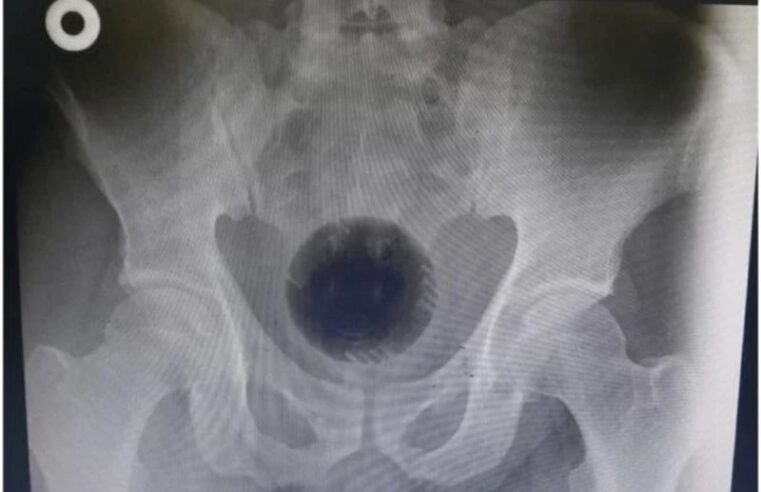

Leia maisHomem passa por cirurgia para retirar bola de 7 cm presa no ânus

ao Hospital Universitário Princess Basma, em Irbid, dois dias depois do incidente, após tentativas frustradas de retirar a bola do ânus com a ajuda de uma colher e uma chave